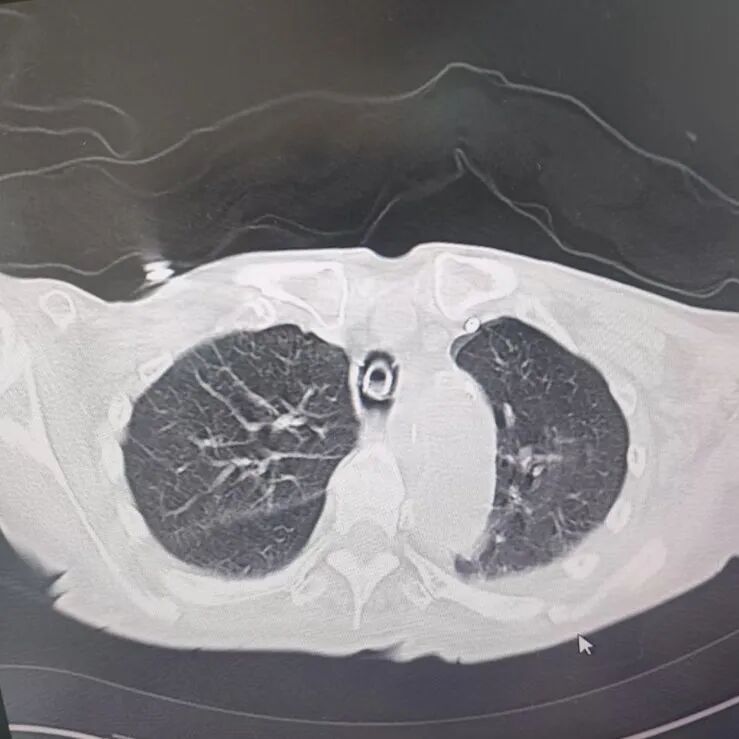

引言 / / Introduction 年近8旬的陳阿姨(化名)因腦梗長(zhǎng)期癱瘓?jiān)诖?,康?fù)期間突然高燒不退,體溫升至39℃,在抗感染過(guò)程中,她并發(fā)高滲性脫水,病情急劇惡化,被緊急送入ICU。此時(shí),她已氣管切開(kāi),依靠呼吸機(jī)維持呼吸,并伴有低蛋白血癥、低鉀高鈉血癥及房顫等多種危重情況,命懸一線! PART. 01 多重泛耐藥菌疊加大量基礎(chǔ)病 治療陷入“死胡同” 呼吸與危重癥醫(yī)學(xué)科及ICU通力協(xié)作,穩(wěn)住患者生命體征。治療過(guò)程中,進(jìn)一步的病原學(xué)檢查結(jié)果令人心驚:陳阿姨的肺部遭遇多種“超級(jí)細(xì)菌”混合侵襲,包括銅綠假單胞菌、鮑曼不動(dòng)桿菌、嗜麥芽窄食單胞菌、金黃色葡萄球菌、木糖氧化無(wú)色桿菌、粘質(zhì)沙雷菌等高度耐藥菌,堪稱(chēng)耐藥菌“大本營(yíng)”。這些細(xì)菌對(duì)常用抗生素幾乎全部耐藥,治療難度高,死亡率高。 治療前患者肺部影像 PART. 02 多學(xué)科強(qiáng)強(qiáng)聯(lián)手 量身定制攻堅(jiān)方案 面對(duì)無(wú)藥可用的困境,呼吸科沒(méi)有放棄!宋剛主任帶領(lǐng)團(tuán)隊(duì)聯(lián)合藥學(xué)部、檢驗(yàn)科、重癥醫(yī)學(xué)科成立多學(xué)科治療組,根據(jù)患者身體情況實(shí)時(shí)調(diào)整用藥,逐一攻破耐藥菌。這場(chǎng)與“超級(jí)細(xì)菌”的拉鋸戰(zhàn)持續(xù)了30多個(gè)日夜。 在醫(yī)護(hù)日夜堅(jiān)守和家屬全力配合下,陳阿姨的感染終于被遏制:高燒退了,肺部陰影消散了!就在即將宣告勝利時(shí),又發(fā)現(xiàn)她存在泌尿感染問(wèn)題,隨即轉(zhuǎn)入泌尿外科協(xié)同治療。當(dāng)宋主任回訪時(shí),看到陳阿姨精神煥發(fā)、體溫平穩(wěn),所有參與救治的人都感慨萬(wàn)分!這場(chǎng)救治,正是呼吸與危重癥醫(yī)學(xué)科攻堅(jiān)耐藥菌硬實(shí)力的生動(dòng)體現(xiàn)! 治療后患者肺部影像 從“無(wú)藥可用”到“絕處逢生”,此次成功救治,集中體現(xiàn)了呼吸與危重癥醫(yī)學(xué)科以耐藥菌精準(zhǔn)診治為核心的學(xué)科特色與技術(shù)優(yōu)勢(shì)。面對(duì)一次次的嚴(yán)峻挑戰(zhàn),科室始終秉持“生命至上、知難而進(jìn)”的信念,以多學(xué)科協(xié)作為平臺(tái),憑借個(gè)體化精準(zhǔn)用藥策略,為患者尋找生機(jī),為更多陷入困境的患者和家庭帶去了實(shí)實(shí)在在的希望。 PART. 03 人民醫(yī)院 人民名醫(yī) 宋剛 主任醫(yī)師 ·葫蘆島市第二人民醫(yī)院呼吸與危重癥醫(yī)學(xué)科主任 ·遼寧省生命科學(xué)學(xué)會(huì)東北呼吸與危重癥醫(yī)學(xué)(PCCM)分會(huì)遼寧省基層委員會(huì)副主任委員 ·遼寧省細(xì)胞生物學(xué)學(xué)會(huì)放射粒子治療專(zhuān)業(yè)委員會(huì)理事 ·遼寧省抗擊新冠肺炎疫情先進(jìn)個(gè)人 ·葫蘆島市勞動(dòng)鑒定委員會(huì)專(zhuān)家?guī)斐蓡T ·葫蘆島市醫(yī)學(xué)會(huì)呼吸內(nèi)科學(xué)分會(huì)第三屆委員會(huì)副主任委員 專(zhuān)業(yè)特色:擅長(zhǎng)呼吸系統(tǒng)疑難及急危重患者的救治,如急慢性支氣管炎、支氣管哮喘、慢性阻塞性肺疾病、肺炎、肺栓塞、肺癌、間質(zhì)性肺疾病、睡眠呼吸暫停綜合征等,尤其擅長(zhǎng)有創(chuàng)無(wú)創(chuàng)機(jī)械通氣、支氣管鏡下相關(guān)檢查及治療(TBNA、氣道支架置入術(shù)、球囊擴(kuò)張等)、全肺灌洗術(shù)等領(lǐng)先技術(shù),發(fā)表國(guó)家級(jí)期刊多篇。